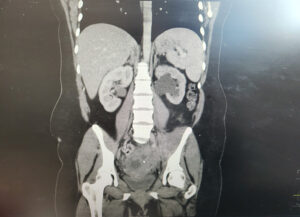

A 32-year-old para 4 woman presented with severe abdominal pain. Laboratory results showed hemoglobin 71 g/L, white cell count 15.4 × 10⁹/L, and C-reactive protein 236 mg/L. She received intravenous co-amoxiclav and metronidazole, along with oral doxycycline.

CT imaging revealed a complex cystic lesion in the pouch of Douglas with involvement of the left ureter and hydroureteronephrosis (Figure 3). MRI confirmed a left TOA with associated iliopsoas myositis and posterior cervical wall invasion (Figure 4). Ultrasound-guided drainage was attempted but was unsuccessful because of adjacent bowel loops. A ureteric stent was inserted, followed by laparoscopic drainage of the abscess (500 mL of pus) and right cystectomy with adhesiolysis. She was tested for tuberculosis and HIV, both of which were negative. She recovered well and was discharged four days postoperatively, with planned ureteric stent removal at follow-up.